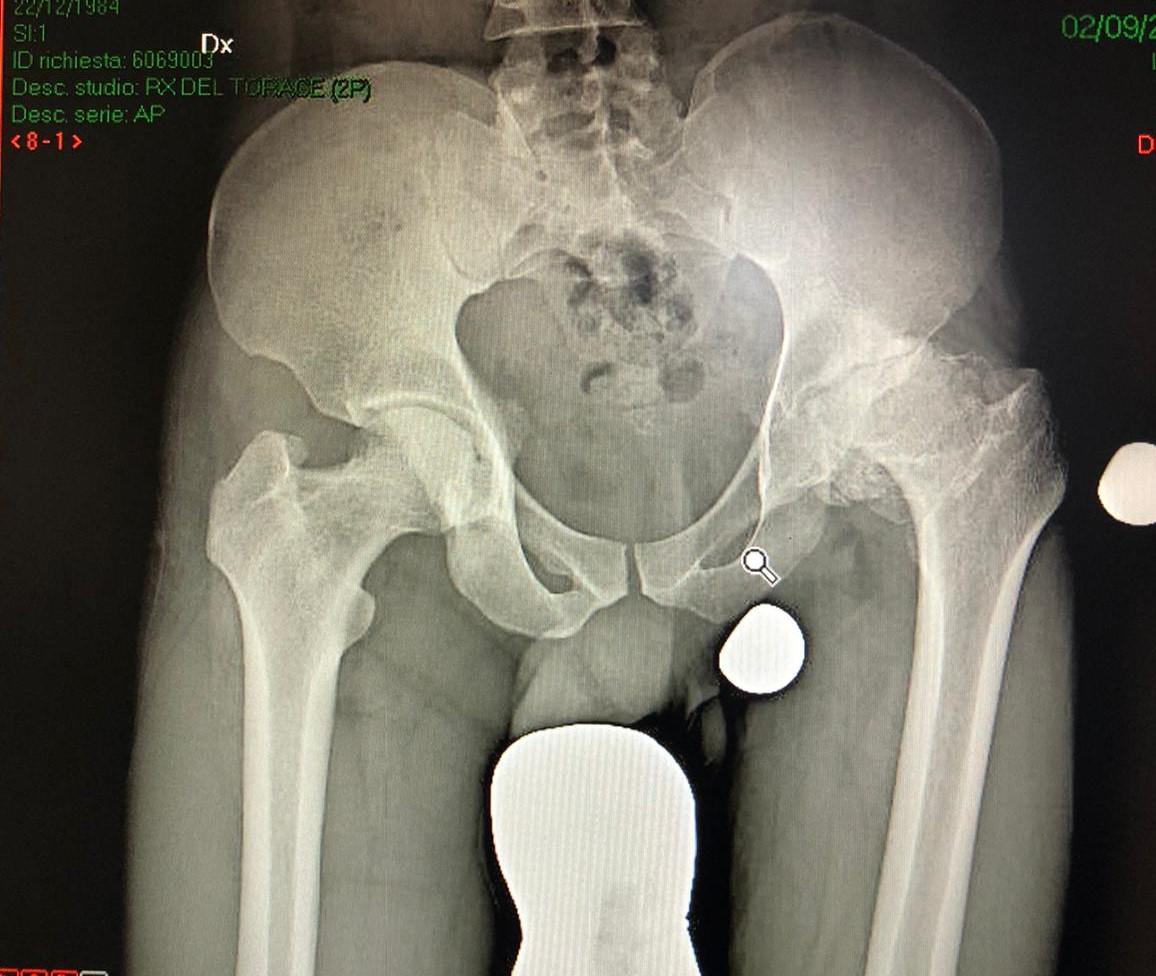

L'anca, come tutte le altre articolazioni, può essere affetta da un numero elevatissimo di malattie. La più comune è l'ARTROSI che consiste nel “consumo” della cartilagine articolare sia della testa femorale che della cavità acetabolare e nell'insorgenza di altre anomalie ossee dei capi articolari come cisti (GEODI), addensamento dell'osso, produzione di osteofiti (OSSIFICAZIONI). Il progressivo deterioramento/ usura si accompagna a dolore, di solito inguinale con irradiazione al gluteo e/o alla faccia interna della coscia, fino al ginocchio ed a notevole diminuzione della mobilità dell'articolazione con conseguente limitazione funzionale, spesso invalidante, caratterizzata da dolore e/o zoppia a camminare o a stare in piedi a lungo, difficoltà a tagliarsi le unghie, a mettere le calze, allacciare le scarpe. L'artrosi può essere primitiva o idiopatica (senza un'apparente causa) o secondaria a condizioni che, per svariati motivi, fanno sì che non si abbia più una perfetta congruenza tra la testa femorale e la cavità che l'accoglie (per esempio in caso di precedenti fratture, malattie congenite o del periodo infantile come ad esempio le displasie, malattie infettive, malattie reumatologiche, malattie metaboliche).

Se si verifica la compromissione vascolare, con riduzione dell’apporto di sangue alla testa femorale, si possono instaurare condizioni di necrosi ossea, con possibile cedimento dell’osso e collasso dello stesso.

ARTROSI DELLANCA 1